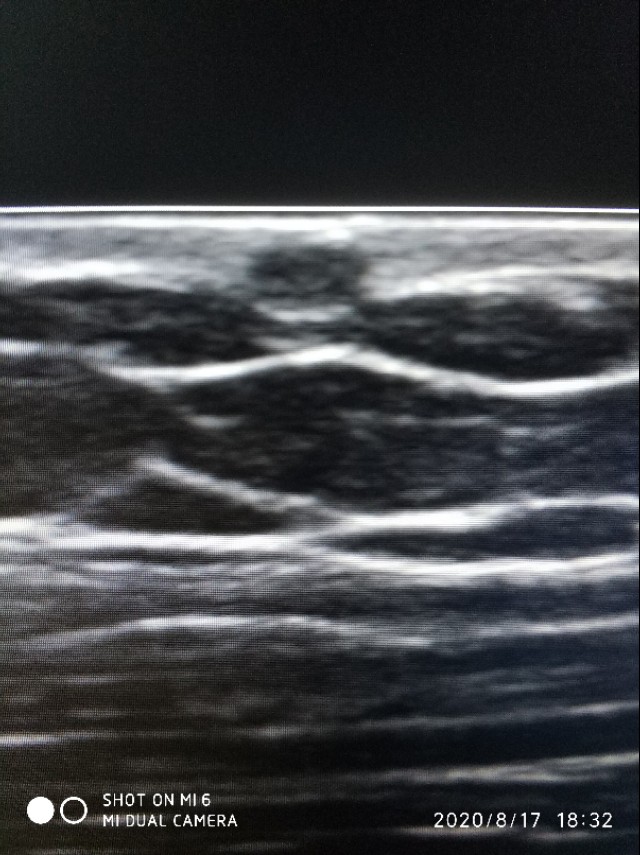

上面是我大腿上的皮脂囊肿,奉献给大家啦。在皮肤上有个小黑点,以前我总是手贱,喜欢抠它挤它,有豆腐渣样的东西出来,至于是什么味道,大家自行脑补。因为害怕有癌变的可能,我现在碰都不碰它了。有些皮脂囊肿增大感染的,其实我也没怎么碰到过,可能没来做超声直接被医生挖掉了。

现在皮肤上囊性包块,表皮样囊肿居多,那么什么是表皮样囊肿呢,它形成的原因可能是由于皮肤外伤或手术,将皮肤上皮组织植入皮下所引起,不过呢,要问病人病史,病人一般是否认包块处有外伤史。还有一种说法是它可能是皮肤单胚层源性的真性良性肿瘤,在没有外伤手术等证据的情况下,后者可能显得更有说服力。表皮样囊肿囊内一般充满表皮角化物或白色颗粒状油脂样物。多发生于手脚部,颈背部,臀部及阴囊。呈圆形或椭圆形,囊壁光滑(未感染或破裂时),生长缓慢,大小不一。在超声上表现为,在位置上位于皮肤的真皮层和皮下脂肪层间。

上图表皮层忽略不计,真皮层为回声增强的一层,再下方是黑白相间的脂肪层,再往下是肌肉层了。

第二点事边界十分清晰,如果囊肿破裂,周围会有积液。第三点是内容物是软化不同的角瓜上皮,超声上表现为细密的腺样强回声有时伴有细密的裂隙样低回声。第四没有血流信号。